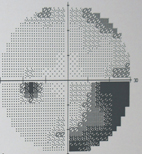

圖三、逐漸惡化的青光眼,造成視野缺損擴大

青光眼進行三部曲,依序是視神經萎縮、再來是視野出現缺陷及最後的視力衰退。視神經萎縮通常來自於視神經盤的凹陷,以及視神經纖維的缺陷;3、5年後,視野開始出現缺陷;再過幾年,才會自覺視力衰退。

就視野缺陷來說,正常人往上可看60度的景物,往下則可看到75度的景物。當一眼的青光眼,另一眼仍正常時,正常眼的視野會彌補過來,因此不太容易感覺出異樣,進而忽略青光眼的威脅,使得青光眼的早期診斷變得很困難。

有人因此形容青光眼:「就像賊一樣,慢慢偷走你的視野。」青光眼視野惡化可分六個階段,第一、第二階段只有最邊緣最角落的視野缺損,第三到第四階段雖缺損的範圍擴大,卻還不易察覺。然而,只要進展到第五、甚至第六階段,大片的視野一下子不見了,視力由原本的1.0-1.2,急遽降到0.2-0.3,讓人措手不及。

如果能在第一或第二階段即察覺不對勁,並避開青光眼的危險因子,通常都還能過著正常生活。一旦進展到第五或第六階段,那就麻煩了,因為想擋也擋不住,視力會像溜滑梯一樣,一路往下掉。正因為青光眼是一個不可逆的病變,定期做眼壓及視神經的檢查非常重要。